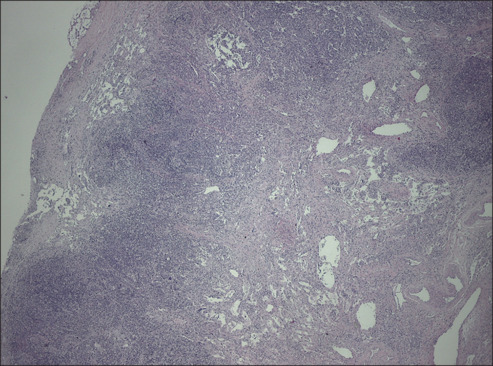

抗病毒治疗的出现改变了人类免疫缺陷病毒感染和卡波西肉瘤患者的预后和临床表现。然而,仍有一些国家的可及性不足,疾病发展为传播形式,结果不利。我们介绍了两例患者,他们的皮肤病变进展了一个月,与艾滋病毒背景下的播散性卡波西肉瘤相一致。开始治疗一个月后,他们因与免疫重建炎症综合征相关的多器官衰竭而入院,最终死亡。

The appearance of antiviral therapy has led to a change in the prognosis and clinical manifestations of patients with human immunodeficiency virus infections and Kaposi's sarcoma. However, there are still countries in which access is inadequate and the disease progresses toward disseminated forms with an unfavorable outcome. We present two patients who presented with skin lesions that progressed for a month, compatible with disseminated Kaposi's sarcoma in the context of HIV. One month after starting treatment, they were admitted for multi-organ failure associated with an Immune reconstitution inflammatory syndrome and eventually died.